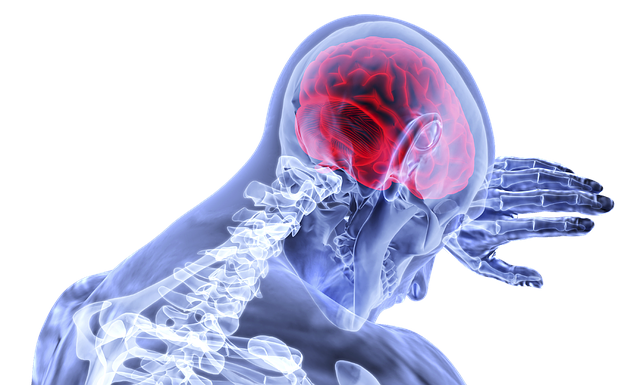

Stress can cause physical pain. Experiencing stress regularly is harmful: high blood pressure is one of its better known side effects, but overstress can lead to a whole range of physical ailments from muscle tissue deterioration to chronic headaches. It is common to hear that joint pain is experienced during moments of prolonged stress. This pain is processed by the central nervous system through a system of neuron transmissions in the spinal cord. The spine then sends signals to the brain, which creates the sensation of pain. Do you ever feel tense when you are stressed? This is a physiological manifestation of the tightness in your muscles. If back muscles are tensing and retracting, they can create misalignments in your spine that cause pressure to the nerves. Simply put stress= pain.

Spinal manipulation restores your spine back into alignment and treats nerves that may have become inflamed due to the build up of stress. Chiropractic and acupuncture are both proven to improve blood circulation. At our office in Park Slope, we use natural methods to boost your body’s natural energy levels, thus helping you cope with stress in a healthier, more effective manner. All of these are important to an effective stress management plan.